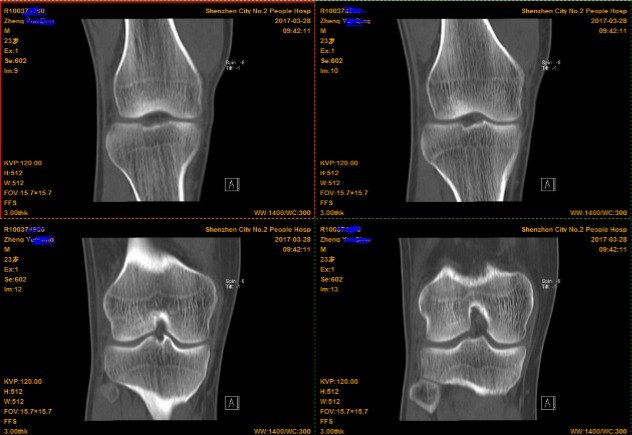

2.CT(以膝关节为例)

由于CT 是三维成像,包括矢状面,冠状面和横断面三个层面的扫描。一张CT片子也是包括医院、姓名、性别、年龄、检查日期、侧别、扫描序列等信息的。

冠状面---是从内向外、从前往后扫描成像。

横断面---是从上向下、从前往后扫描成像。